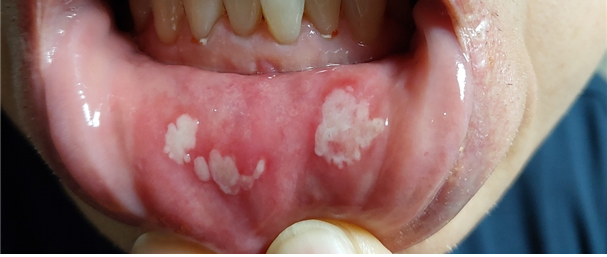

(사진제공: 대한치과의사협회)

실제로 구매 고객에게 ‘치은부종’이 유발된 것은 물론, 구강 내 ‘점막궤양’이 발생한 사례도 있다.